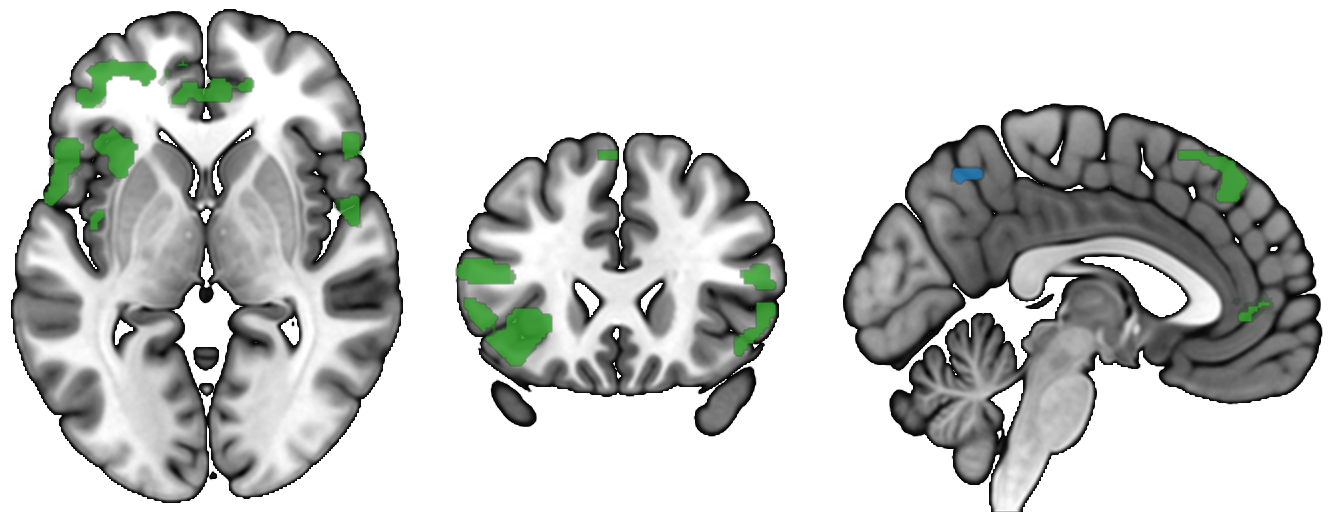

The sagittal slice is not cut off at the bottom. The brain field of

view only shows a limited amount of the neck. You can see that the

sagittal slice is perfectly aligned with the coronal images and the

sagitall rendering by including a coronal slice that includes more

of the spinal column, for example y = -50mm in MNI space:

import gl

gl.resetdefaults()

#open background image

gl.loadimage('spm152')

#open overlay: show positive regions

gl.overlayload('spmMotor')

gl.minmax(1, 4, 4)

gl.opacity(1,50)

#open overlay: show negative regions

gl.minmax(2, -4, -4)

gl.colorname (2,"3blue")

gl.mosaic("C 20 -50 S 0 20 S X R 0");

It is true that your image is longer in the A-P direction (Y) than the I-S (Z) direction, so the axial slice will appear taller than the coronal and sagittal slices. This reflects the field of view of your image. You may want to use the semicolon ";" to place your axial slices on a separate row from the coronal and sagittal slices. The screen height for axial slices is the Y-dimension, while it is the Z-dimension for the coronal and sagittal slices. In contrast, the screen width is the X-dimension for the axial and coronal slices, but the Y dimension for sagittal slices. You can always create your own template images with any field of view you wish.